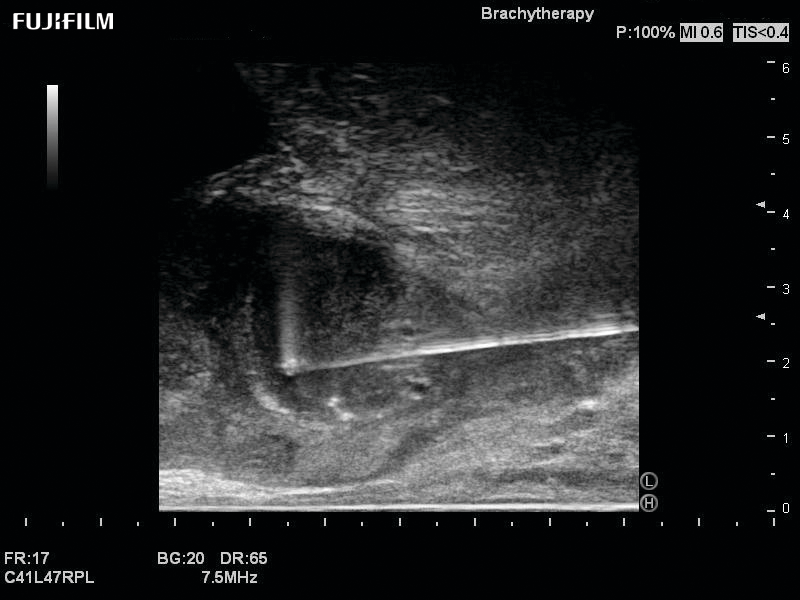

Ideal transducer for Transperineal Biopsy, Hydrogel Spacer Placement, Brachy LDR & HDR, Cryo, and MPMRI procedures.